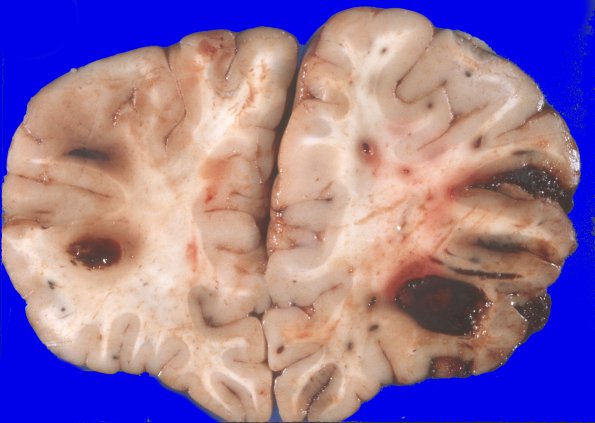

Washington University Experience | NEOPLASMS (HEMATOLYMPHOID) | Granulocytic Sarcoma | 4A1 Leukemic nodules (Case 4) gross 3

4A1-5 There is bilaterally symmetrical cerebral edema causing flattening of the gyri and narrowing of the sulci over both hemispheres. Cross sections of the bilateral cerebral hemispheres disclose multiple well circumscribed areas of hemorrhage, many at the cortical gray/white junction. These measure from approximately 1 mm to 2 cms in diameter. In some cases, the central portion of the hemorrhage appears to be made up of a pale appearing substance.